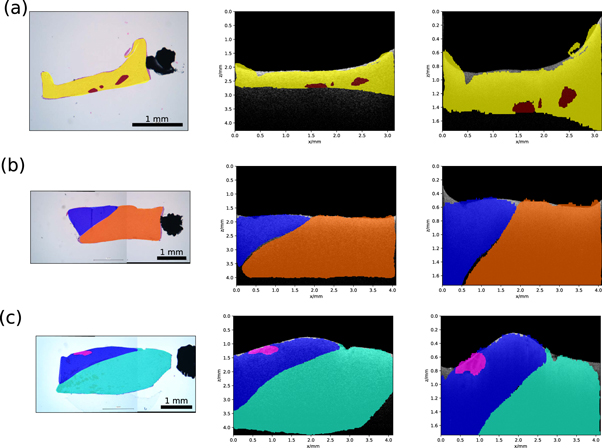

The presented pipeline was performed on 1630 histological images and their corresponding OCT images. In 75% of the cases the histological sample stayed in the shape given by the embedding process. These samples were then to transform the histological labels onto the corresponding OCT images. Examples of a successful transformation are shown in figure 8. For the remaining 25%, the sample changed its shape too much during the histological preparation (e.g. tearing of the tissue), which disabled usage of the shape information needed for the transformation. The evaluation of the U-Net, used for the creation of binary masks, was performed on the independent test data set. The test data set consisted of 342 OCT images. The test data set was processed with the U-Net and was compared against the ground truth segmentations by using the dice score (Dice 1945). The network achieved a dice score of 0.9970, which indicates that the U-Net adapted very well to the binary segmentation task. Additionally, the U-Net segmentation of background and foreground was compared to a graph search algorithm, which can be alternatively used for the creation of binary masks (Duan et al 2012). The test dataset was also used for this task. For both algorithms the tissue surface was extracted from the resulting binary masks. The absolute difference to the ground truth was calculated. The graph search algorithm achieved a median difference of 2.0 [1.0; 11.0] pixel, while the U-Net achieved a median difference of 0.0 [0.0; 1.0] pixel. The values in the square parentheses indicate the first and third quartile. The processing time of the U-Net was 0.2 s for one OCT image, while the graph search algorithm took around 30 s for one OCT image. In order to evaluate the registration process based on the OCT height maps (registration of the SD-OCT volume onto the SS-OCT volume), the top view intensity projections of the volumes were also put through the same registration process. The top view intensity projection, also called en face view, is usually used for visualization of the top view of an OCT volume V(x, y, z) and is defined as the mean intensity along the depth axis z

Figure 8. Transformation results for three exemplary samples: histological image and label (left), corresponding SS-OCT image and transferred label (centre) and SD-OCT image with transferred label. Meaning of the colors is as follows: yellow—white matter with 0% tumour infiltration, red—coagulation in white matter, blue—grey matter with 0% tumour infiltration, orange—edema in white matter, pink—blood in grey matter and cyan—white matter with 0%–30% tumour infiltration.

Download figure:

Standard image High-resolution imageThe registration process was run again for the height maps and the en face images over 164 samples. For each registration the final value of the mutual information was saved. The mean mutual information for the registration of the height maps was 1.92 ± 0.59, while the mean mutual information for the registration with the en face images was 0.37 ± 0.25. The results show that the registration based on the height maps gave a higher mutual information value than the registration based on intensity information. This indicates that the registration with the height maps delivered a better registration result, because the mutual information increases with higher similarity between the images. The topological information of the sample was better suited for the registration in this case, because the intensity values of the homogeneous brain tissue did not show a lot of features, like vessels, which could have helped with an intensity based registration approach. The evaluation of the label transfer process was done with 30 manually chosen histological images and their corresponding OCT images from the two systems. The sample size for this analysis was rather low compared to the overall number of samples, because samples that show clearly visible inner structures within the OCT images and the histological image are rare. For the evaluation the histological image was transformed onto the OCT images with the help of the displacement fields, which were determined prior for the histological labels. Afterwards corresponding feature points were manually selected between the transformed histological image and the respective OCT image. The Euclidean distance was calculated between the corresponding points. The mean Euclidean distance between feature points of the transformed histological image and the OCT images was 200 ± 120 μm. This error accounts for a 6% displacement relative to the minimum sample width of 3 mm.